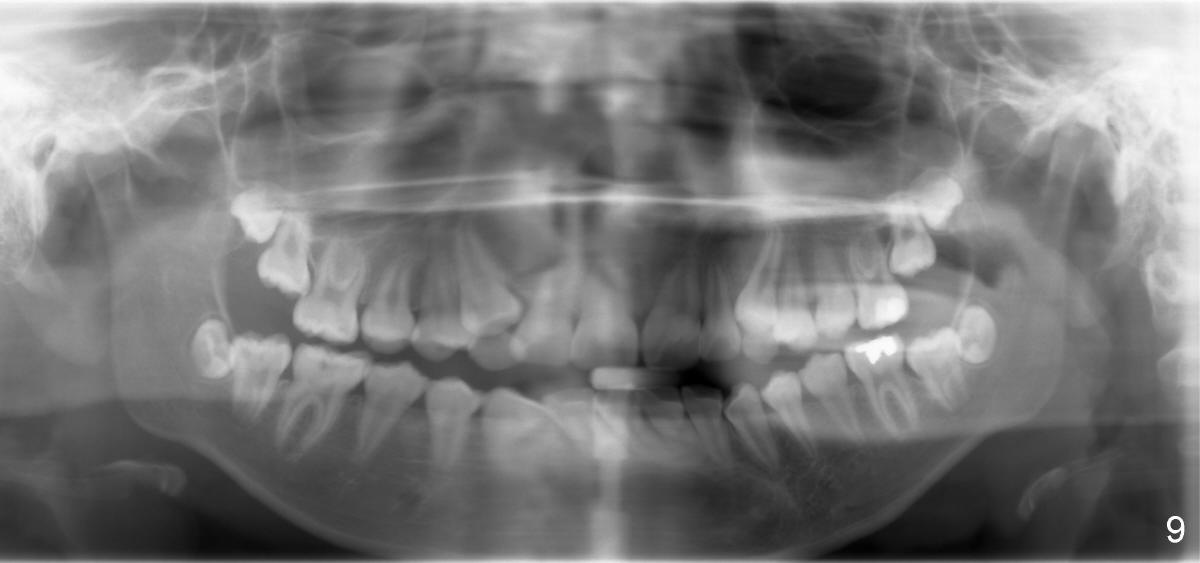

Treatment plan for Nathalie (12 years 9 months old) after banding & bracketing (Visit 1 (Fig.1-3, 7 and 8): use 14 niti)

1. Will the upper anterior teeth erupt more following wire sequence (as wires become straightened, thicker and stiffer, Fig.1)?

7. Expand spaces for u3s using 18 ss wire until they erupt (Fig.1-3, 7; Visit 3)